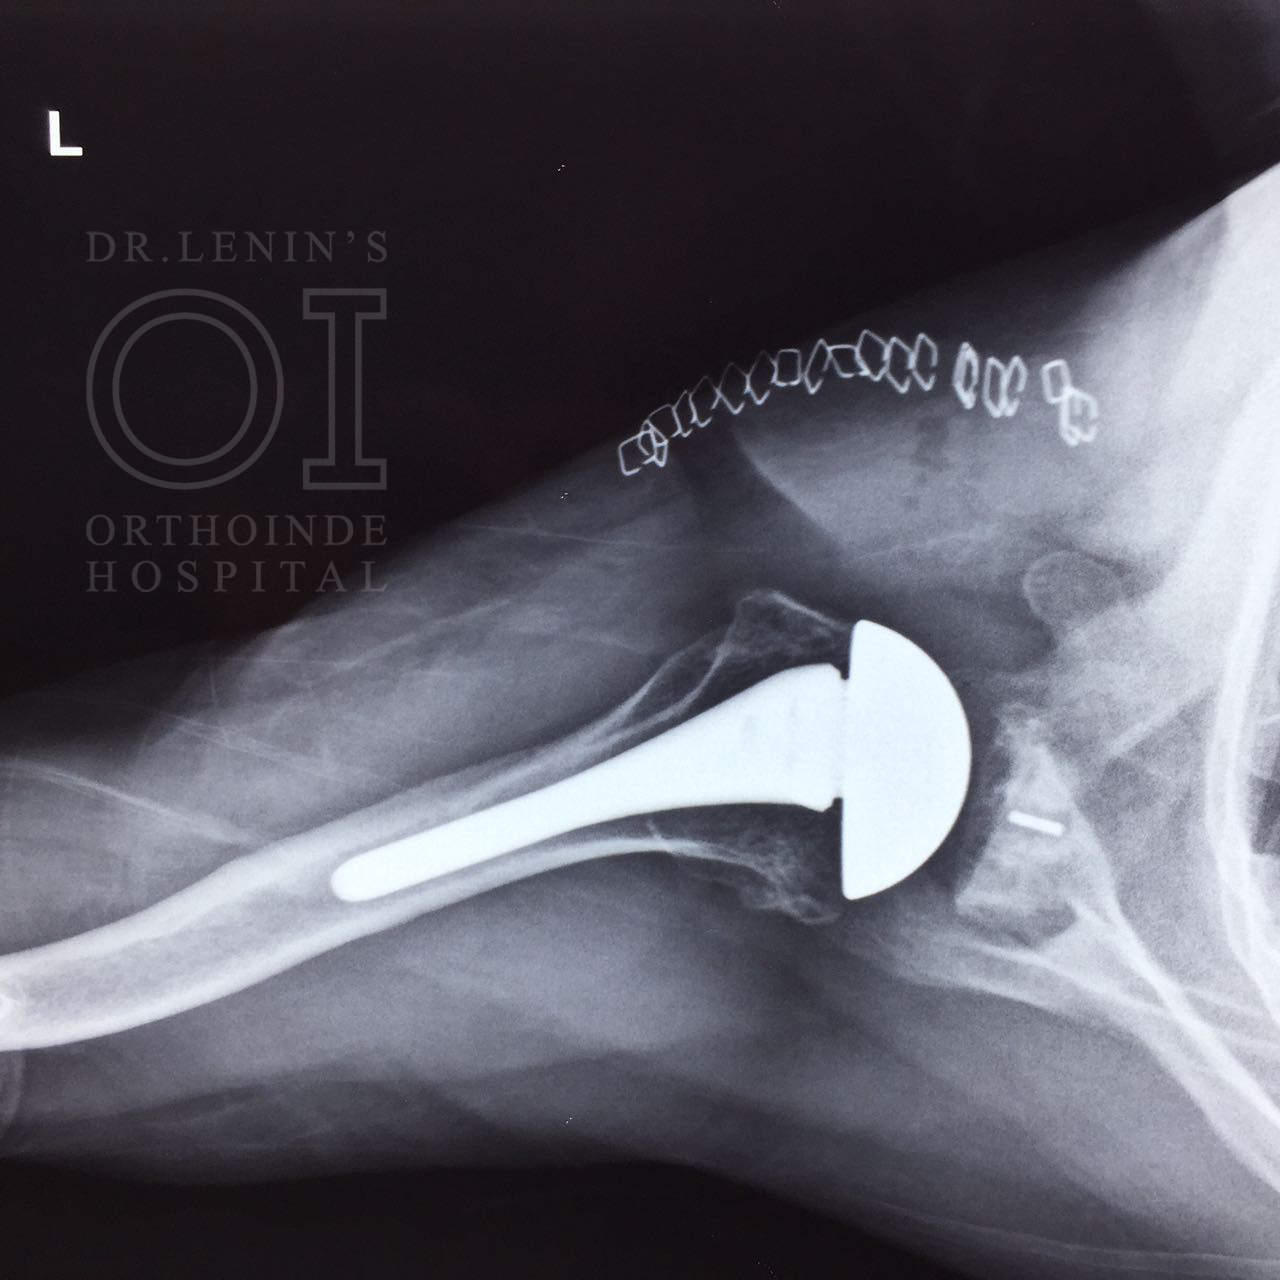

Hemi Arthroplasty

A hip hemiarthroplasty is a surgical procedure where half of the hip is replaced. This procedure is typically used to repair a broken or fractured hip but can also be used to treat a hip damaged by arthritis.

Shoulder hemiarthroplasty is a shoulder replacement in which the damaged humeral head is replaced with a prosthetic humeral head. Shoulder arthroplasty is a rapidly evolving area of orthopedics focused on treating specific, painful ailments of the glenohumeral articulation.

Total Replacement

The standard total shoulder replacement involves replacing the arthritic joint surfaces with a highly polished metal ball attached to a stem, and a plastic socket.

These components come in various sizes. They may be either cemented or press fit into the bone. If the bone is of good quality, we can use a non-cemented (press-fit) humeral component. If the bone is soft, the humeral component may be implanted with bone cement. In most cases, an all-plastic glenoid (socket) component is implanted with bone cement.

Reverse Shoulder Replacement

In a reverse total shoulder replacement, the rounded head of the upper arm bone is removed Using screws and special tools, and a plastic socket is attached to the remaining bone. The socket of the shoulder blade is also removed and is then replaced with a metal ball.